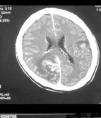

Paciente varón de 40 años, con antecedentes de tabaquismo y prácticas sexuales de riesgo, que consulta por un cuadro progresivo de unas 2 semanas de evolución de pérdida de fuerza en hemicuerpo izquierdo, alteraciones visuales y cefalea. No se refería fiebre ni cuadro constitucional. Exploración física general sin hallazgos, manteniendo el paciente buen nivel de conciencia y aceptable estado general. En la exploración neurológica se podía constatar una hemianopsia homónima izquierda, paresia facial central izquierda, hemiparesia izquierda (3/5) de predominio crural, con hemidisestesia y reflejos osteotendinosos exaltados ipsilaterales. Los análisis de laboratorio mostraron linfopenia (600/(l), con cifras de hemoglobina y plaquetas normales, estudios de coagulación y bioquímicos dentro de la normalidad, incluyendo función renal, perfil hepático, LDH y sistemático de orina. La radiografía de tórax y el ecocardiograma transtorácico fueron normales. Se realizó una TC craneal que evidenciaba múltiples lesiones focales supratentoriales, hiperdensas en el estudio sin contraste en relación con hemorragia de las mismas, con realce tras contraste intravenoso y edema vasogénico periférico (fig. 1). La RM craneal mostraba múltiples lesiones focales supra e infratentoriales, hiperintensas en las secuencias potenciadas en T1 y en T2, muchas de ellas con realce heterogéneo tras la administración de contraste y con hemorragia (fig. 2). Se completaron estudios microbiológicos que confirmaron infección por VIH con serología positiva (ELISA y W. Blot), carga viral de 4,36 log10 copias/ml, CD4: 11,9% (71/mm3), serología toxoplasma IgG positiva, despistaje negativo de otras coinfecciones y patologías oportunistas (serología LUES, VHB y VHC negativas, baciloscopias y cultivo micobacterias de esputo y orina negativos, test de Mantoux negativo, determinación de antígeno criptocócico en suero negativo y PCR de citomegalovirus en plasma negativa).